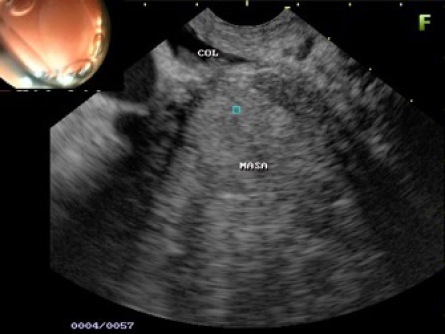

Este examen se utiliza para evaluar una anormalidad, como una protuberancia o lesiones, detectadas en una endoscopia anterior. La ultrasonografía EUS ofrece una imagen detallada de la protuberancia o lesión, que puede ayudar al médico a determinar su naturaleza y a decidir cuál es el mejor tratamiento.

Este examen ayuda al médico a determinar el alcance de ciertos tipos de cáncer de los sistemas digestivo y respiratorio. También le permite evaluar con precisión la profundidad del cáncer y si éste se ha extendido a las glándulas linfáticas o estructuras vitales adyacentes, como por ejemplo los vasos sanguíneos más importantes. En algunos pacientes, la ultrasonografía EUS puede utilizarse para obtener biopsias con aguja de una protuberancia o lesión que ayudan al médico a determinar cuál es el tratamiento más adecuado.

- Intervencionismo/ Biopsia dirigida de tumores o adenopatía.